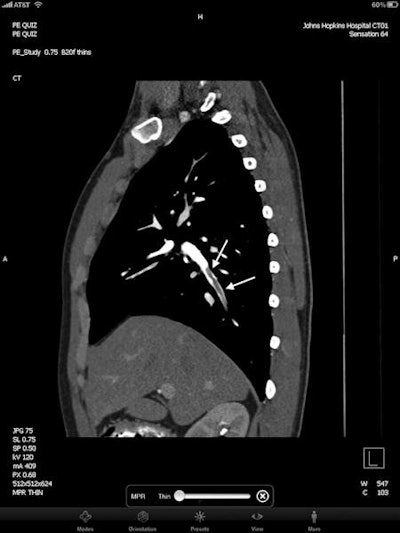

| Axial image (top) and sagittal multiplanar reconstruction (bottom) from contrast-enhanced MDCT viewed on the iPad. Arrows show right lower lobe segmental pulmonary embolism. All images courtesy of Dr. Pam Johnson. |

Although interpretation speed wasn't measured during the study, the reviewers were surprised at how fast the iPad was, Johnson said. Image load time ranged from 700 to 1,000 slices per second at 512 x 512 resolution.

"Both readers commented that the iPad seemed like a faster method of display, and both selected the narrow reconstructed sections as primary means of review, generally in the range of 600-800 slices," the authors wrote.